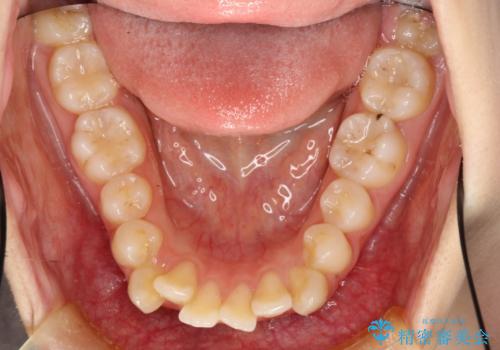

- 口元の突出感を気にして来院された患者様です。

上下左右の第一小臼歯4本を抜歯して口元を下げる治療計画としました。

3年半ほどで終わる予定でしたが、途中引っ越し、出産、引っ越し、出産を繰り返し、なかなか来院することができず、装置を外すまでに8年以上の期間がかかってしまいました。